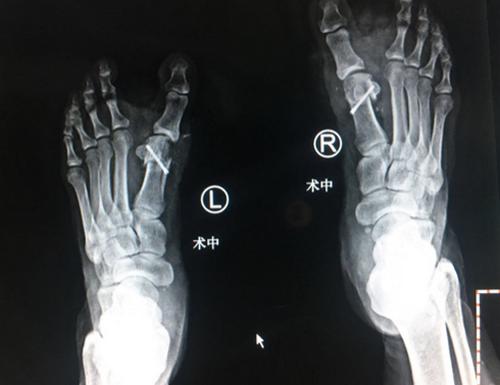

石荣剑院长为李大姐进行了双足踇外翻矫形术。麻醉师采用超声引导下神经阻滞,手术团队采用不到一厘米切口,4毫米进口超声磨锯微创截骨,手术全程无血渗出,完美修整踇外翻。

术中X线

手术很成功,术后第二天几乎就感觉不到疼痛了,术后三天换药基本看不到伤口,李大姐很开心。